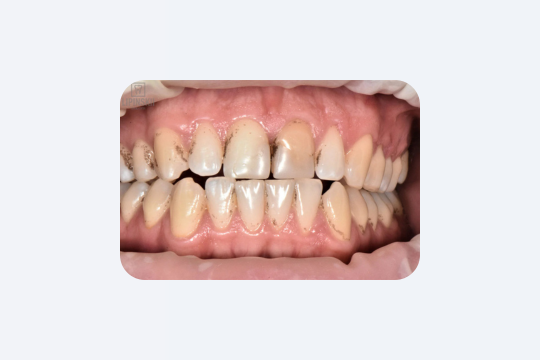

4. Ночной бруксизм (скрежет зубами)

Бруксизм — бессознательное сжатие или скрежетание зубами — бывает и днём, и ночью. Ночное скрежетание особенно опасно: силы напряжения челюстей во сне могут превышать дневные. В результате эмаль стирается, появляются микротрещины и сколы зубов и пломб. Со временем зубные коронки становятся заметно короче.

Кроме того, постоянная перегрузка приводит к перенапряжению сустава. Особенно люди с бруксизмом замечают по утрам боль в челюсти или головную боль, хотя сами приступы ночного скрежета часто остаются незаметными.